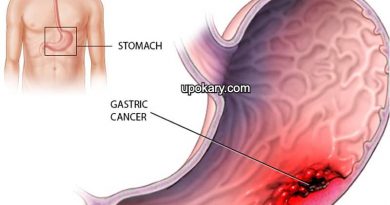

গেঁটেবাত হয় যখন আপনার জয়েন্টে ইউরেট স্ফটিক জমা হয়, যার ফলে গেঁটেবাত আক্রমণের প্রদাহ এবং তীব্র ব্যথা হয়। আপনার রক্তে ইউরিক অ্যাসিডের উচ্চ মাত্রা থাকলে ইউরেট স্ফটিক তৈরি হতে পারে। আপনার শরীর ইউরিক অ্যাসিড তৈরি করে যখন এটি পিউরিনগুলিকে ভেঙে দেয়।

লাল মাংস এবং লিভারের মতো অঙ্গ মাংস সহ নির্দিষ্ট কিছু খাবারেও পিউরিন পাওয়া যায়। পিউরিন-সমৃদ্ধ সামুদ্রিক খাবারের মধ্যে রয়েছে অ্যাঙ্কোভি, সার্ডিন, ঝিনুক, স্ক্যালপস, ট্রাউট এবং টুনা। অ্যালকোহলযুক্ত পানীয়, বিশেষ করে বিয়ার, এবং ফলের চিনি (ফ্রুক্টোজ) দিয়ে মিষ্টি করা পানীয়তে ইউরিক অ্যাসিড উচ্চ মাত্রায় থাকে।

সাধারণত, ইউরিক অ্যাসিড আপনার রক্তে দ্রবীভূত হয় এবং আপনার কিডনি দিয়ে আপনার প্রস্রাবে যায়। কিন্তু কখনও কখনও হয় আপনার শরীর খুব বেশি ইউরিক অ্যাসিড তৈরি করে বা আপনার কিডনি খুব কম ইউরিক অ্যাসিড নিঃসরণ করে।

যখন এটি ঘটে, তখন ইউরিক অ্যাসিড তৈরি হতে পারে, জয়েন্ট বা পার্শ্ববর্তী টিস্যুতে ধারালো, সূঁচের মতো ইউরেট স্ফটিক তৈরি করতে পারে যা ব্যথা, প্রদাহ এবং ফোলাভাব সৃষ্টি করে।